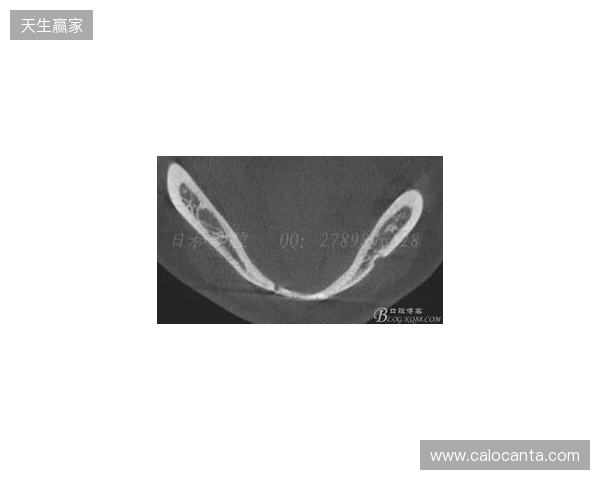

韦林顿确诊上唇部贯通伤;11、21牙半脱位;上颌前牙区牙槽骨骨折

根据医院的检查结果,韦林顿·席尔瓦的上唇部受伤程度较为严重,属于贯通伤,已经进行了清创缝合。这种类型的伤势不仅影响外观,还可能对球员的饮食和发声造成影响。更为严重的是,他的上颌前牙区还出现了骨折,意味着席尔瓦在恢复期间将面临长时间的治疗和康复过程。

球员的第11和第2EMC易倍app1牙出现了半脱位的情况,这可能会导致他在恢复后需要进行进一步的牙科治疗,甚至有可能影响到他今后的职业生涯。医生表示,虽然通过手术和治疗可以恢复,但心理层面的恢复同样重要。